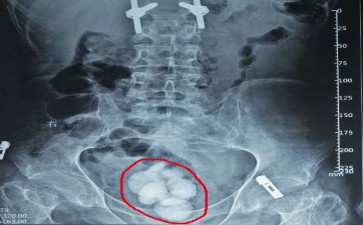

膀胱这个尿液暂存仓库 咋攒出了坚硬杂物

在人体的泌尿 “储运系统” 中,膀胱就像一个弹性十足的 “尿液暂存仓库”,白天收集肾脏送来的尿液,等达到一定量就发出 “排泄信号”。可当膀胱结石出现,就像仓库里莫名攒起了 “坚硬杂物”,不仅占地方,还会搅得整个仓库不得安宁。

这些 “坚硬杂物” 的出现,和仓库的 “使用习惯” 密切相关。肾脏或输尿管的结石 “掉落” 进来,如同其他地方的碎石滚进了仓库;长期憋尿让尿液在仓库里 “久存变质”,水分被过度吸收,杂质慢慢凝结成块;前列腺增生导致尿液排出不畅,好比仓库出口被堵住,残留的尿液成了结石滋生的 “温床”。起初,小结石可能只是在仓库里 “安静待着”,让人没啥感觉;可随着它们变大,排尿时就会出现刺痛,像仓库里的杂物硌到了内壁,严重时还会造成梗阻,让尿液排不干净,进而引发感染,出现尿频、尿急等 “仓库警报”。